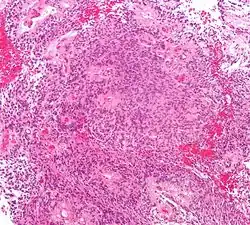

| Micrograph of an ependymoma. H&E stain. | |

Ependymomas are composed of cells with regular, round to oval nuclei. There is a variably dense fibrillary background. Tumor cells may form gland-like round or elongated structures that resemble the embryologic ependymal canal, with long, delicate processes extending into the lumen; more frequently present are perivascular pseudorosettes in which tumor cells are arranged around vessels with an intervening zone consisting of thin ependymal processes directed toward the wall of the vessel.[5]

The World Health Organization classifies ependymomas as Grade I-III. Grade I tumors are low-grade and include the subependymoma subtype, which is more common in adults. Grade II tumors include myxopapillary and conventional ependymoma, which are identified by the presence of perivascular pseudorosettes. Grade III anaplastic ependymomas are the most severe and fast-growing tumors.[4]